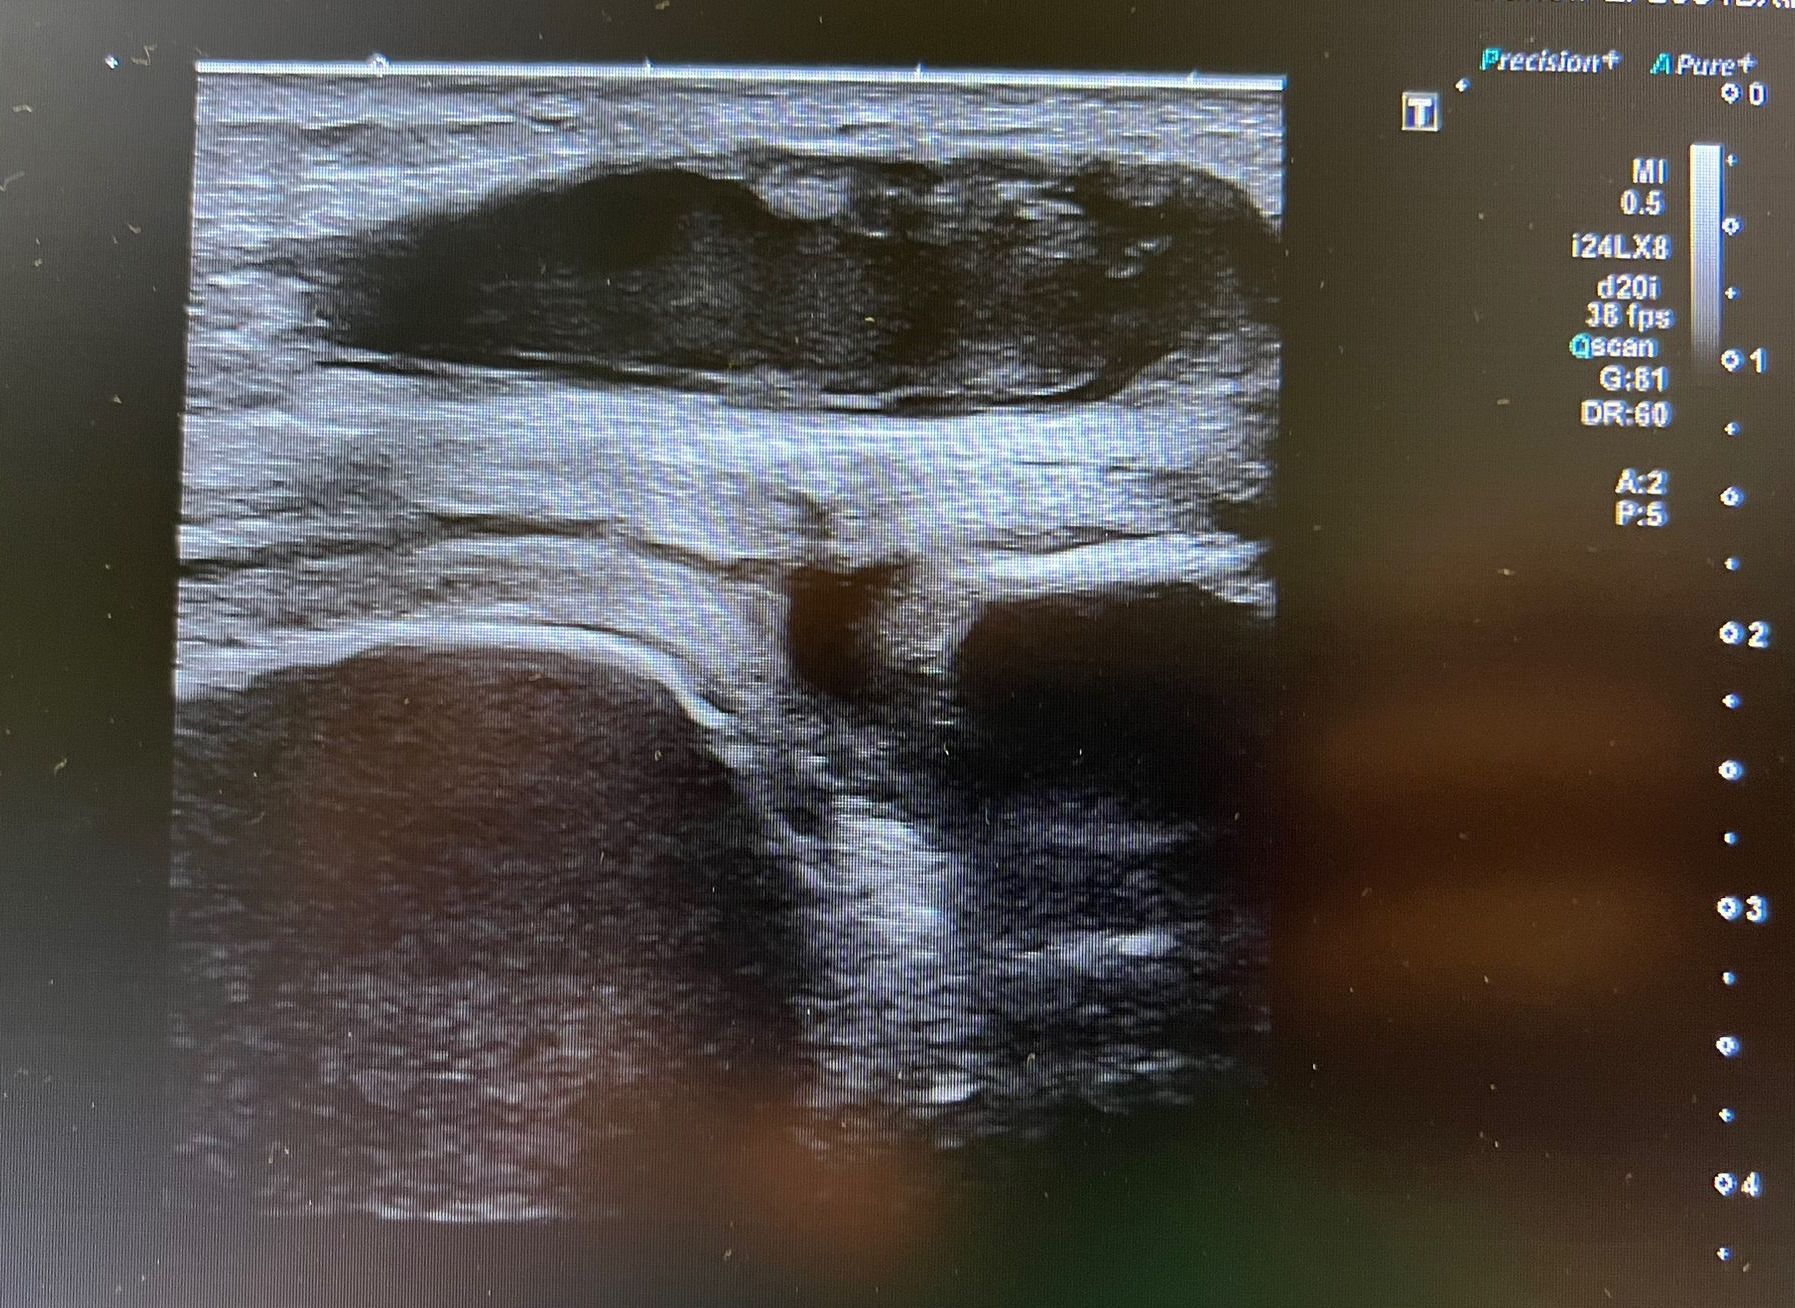

Se realiza ecografía clínica en la que se aprecia colección heterogénea en bursa prerrotuliana así como edema de partes blandas. No aumento de líquido ni colecciones a nivel intraarticular sugestivas de artritis séptica.

• Se realiza punción de la bursa ecogiada para cultivo de la colección.

En el caso de un paciente que refiere dolor, eritema y aumento de temperatura en una articulación y, sobre todo, tras la realización de una técnica invasiva, debemos descartar en primer lugar una artitis séptica por la gravedad del cuadro. La ecografía es una herramienta útil y rápida, que nos puede ayudar a tomar decisiones ante esta clínica. Es importante para poder descartar dicha patología la ausencia de líquido y/o colecciones intraarticulares.